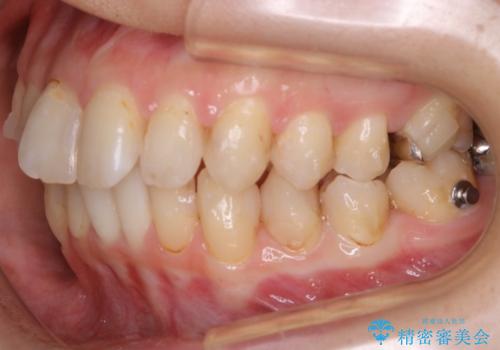

- 前歯のガタつきと噛み合わせの改善を希望してご来院されました。

目立たない装置での矯正治療をとのことでインビザラインを用いた非抜歯矯正を行うこととなりました。

虫歯の治療などが必要な部位がある場合には矯正治療に先立ち全体の状態をよくする術前治療が行われます。